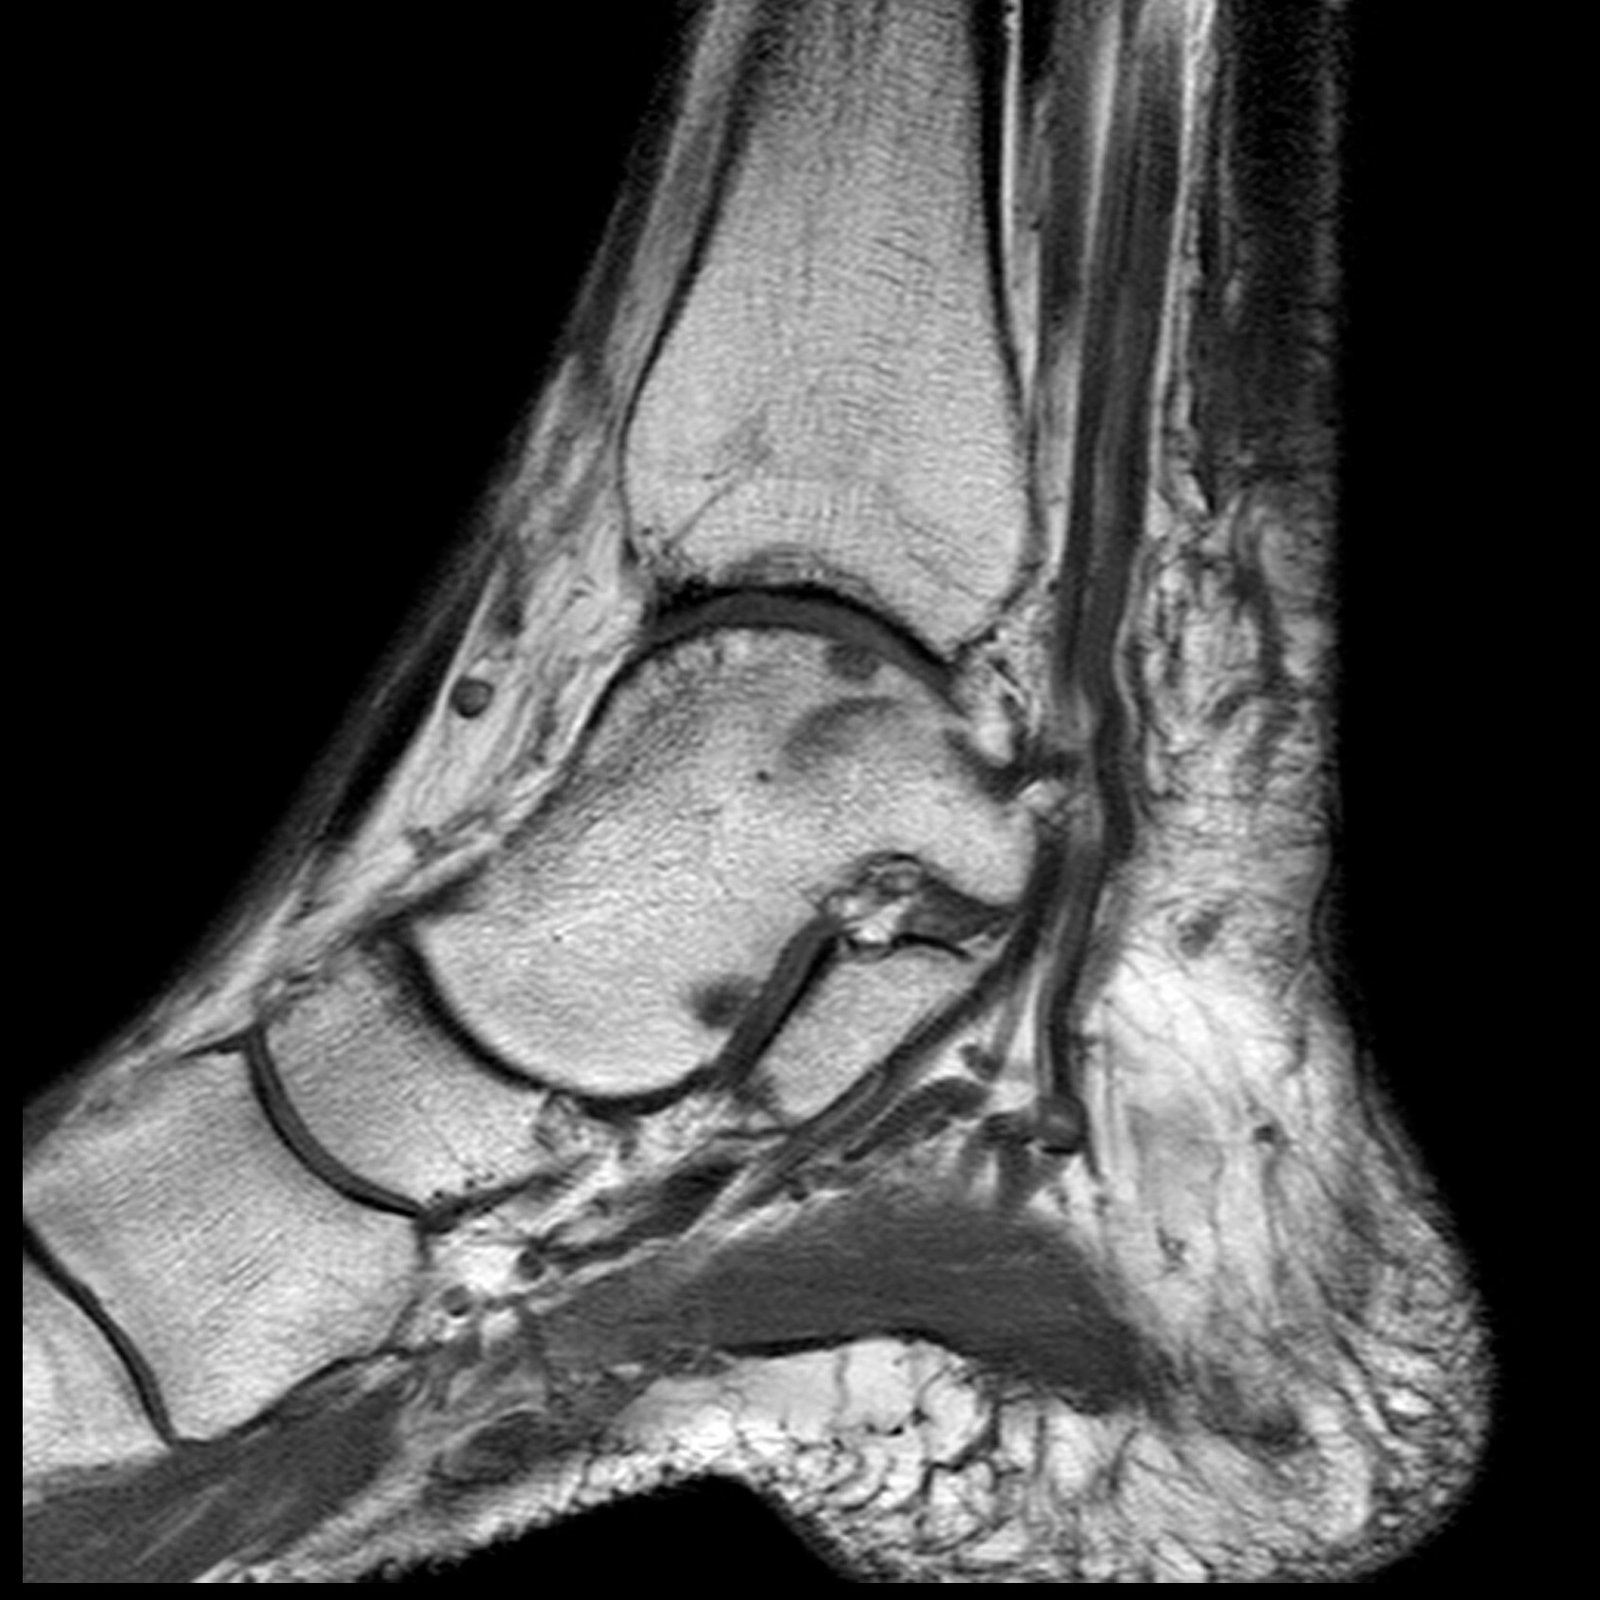

Orthopedic